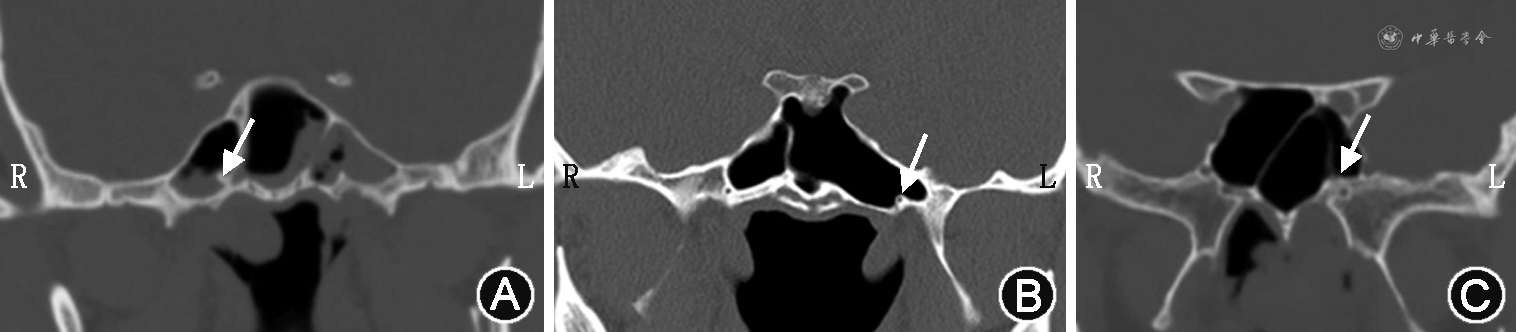

翼管神经由岩浅大神经和岩深神经在破裂孔处汇合而成,与翼管动脉伴行,出翼管前孔后直接融入翼腭神经节[3],然后又分出腭神经、鼻支、咽支和眶支,分别支配上腭部黏膜、鼻腔黏膜、鼻咽部部分黏膜腺体以及泪腺[4, 5, 6]。翼管位于蝶腭孔的后方,外口呈漏斗形。依据翼管在蝶窦中的走行,可将其分为3种类型:Ⅰ型完全突出于蝶窦腔;Ⅱ型部分突出于蝶窦腔;Ⅲ型完全包埋于蝶骨体内(图1)。Yazar等[7]对150例患者进行鼻窦CT扫描观察翼管形状,发现Ⅰ型占10%,Ⅱ型占54%,Ⅲ型占36%,这对于术前评估、选择入路方式具有重要的参考价值。